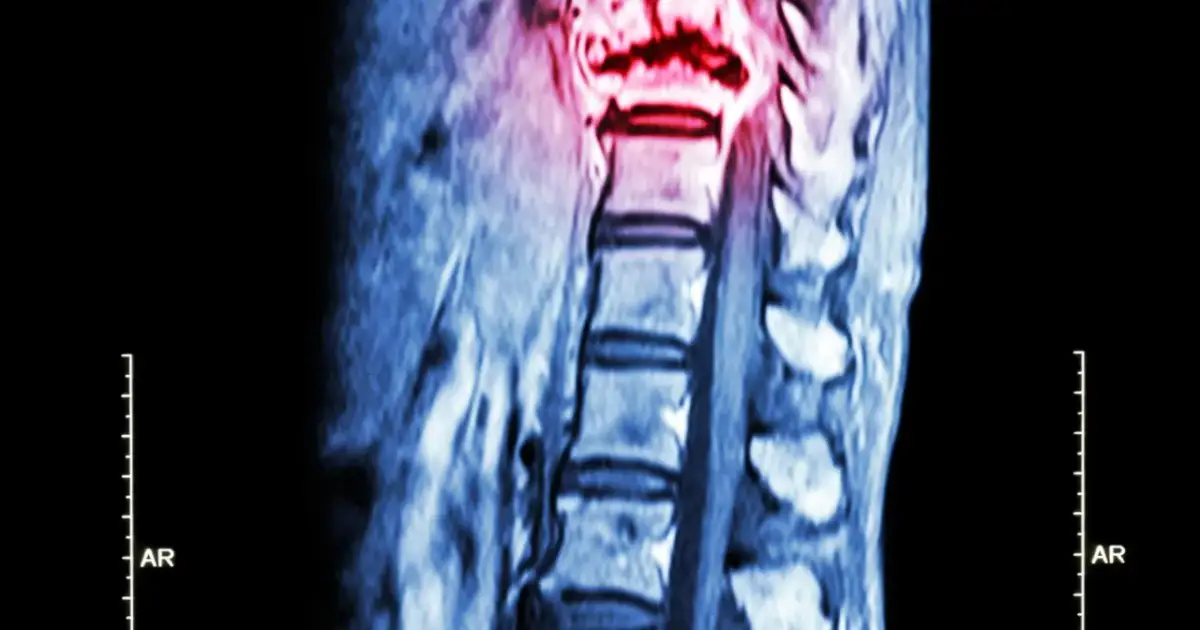

Ucisk na rdzeń kręgowy: Stan nagły, który wymaga natychmiastowej reakcji

Ucisk na rdzeń kręgowy to jedno z najgroźniejszych powikłań przerzutów do kości, które wymaga natychmiastowej interwencji medycznej. Najczęściej jest spowodowany przerzutami do kręgosłupa, które rosnąc, zaczynają uciskać na delikatne struktury nerwowe. Czas odgrywa tu kluczową rolę, ponieważ opóźnienie w leczeniu może prowadzić do trwałych i nieodwracalnych uszkodzeń.Objawy neurologiczne: Od bólu pleców po drętwienie i niedowład kończyn

Objawy neurologiczne związane z uciskiem na rdzeń kręgowy są bardzo zróżnicowane, ale zawsze alarmujące. Mogą obejmować silny, uporczywy ból pleców, który często promieniuje do kończyn. Obserwuje się również osłabienie mięśni, drętwienie lub mrowienie w kończynach, a w bardziej zaawansowanych przypadkach niedowłady, czyli częściową utratę ruchomości. Jeśli zauważymy takie symptomy u pacjenta onkologicznego, należy działać bez zwłoki.

Zaburzenia kontroli zwieraczy: Alarmujący sygnał z kręgosłupa

Jednym z najbardziej poważnych i alarmujących objawów ucisku na rdzeń kręgowy jest zaburzenie kontroli zwieraczy, czyli nietrzymanie moczu i kału. To sygnał, że ucisk jest już bardzo zaawansowany i zagraża funkcji nerwów kontrolujących te procesy. W takiej sytuacji natychmiastowa interwencja medyczna jest absolutnie konieczna. Należy pamiętać, że brak leczenia w ciągu 24 godzin od wystąpienia tych objawów może niestety prowadzić do trwałego uszkodzenia rdzenia kręgowego i nieodwracalnej utraty funkcji.

- Rezonans magnetyczny (MRI): Jest to badanie szczególnie cenne w ocenie struktur miękkich, takich jak szpik kostny i rdzeń kręgowy. Jest niezastąpione w diagnostyce ucisku na rdzeń.